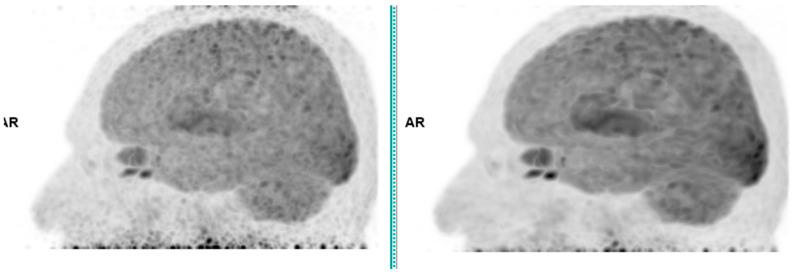

This study assesses the clinical deployment of SubtlePET™, a commercial AI-based denoising algorithm, across three radiotracers-18F-FDG, 68Ga-PSMA-11, and 18F-FDOPA-with the goal of improving image quality while reducing injected activity, technologist radiation exposure, and scan time. A retrospective analysis on a digital PET/CT system showed that SubtlePET™ enabled dose reductions exceeding 33% and time savings of over 25%. AI-enhanced images were rated interpretable in 100% of cases versus 65% for standard low-dose reconstructions. Notably, 85% of AI-enhanced scans received the maximum Likert quality score (5/5), indicating excellent diagnostic confidence and noise suppression, compared to only 50% with conventional reconstruction. The quantitative image quality improved significantly across all tracers, with SNR and CNR gains of 50-70%. Radiotracer dose reductions were particularly substantial in low-BMI patients (up to 41% for FDG), and the technologist exposure decreased for high-exposure roles. The daily patient throughput increased by an average of 4.84 cases. These findings support the robust integration of SubtlePET™ into routine clinical PET practice, offering improved efficiency, safety, and image quality without compromising lesion detectability.